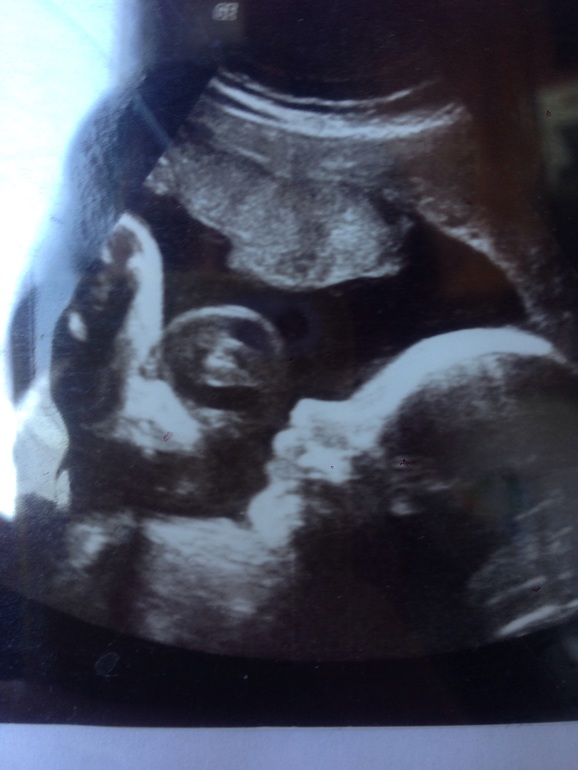

вот узи моего сынули. губища верхняя огого, плюс мне тогда сказали что кости носа маловаты, а это маркер хромосомного нарушения. высылаю фото Арсю. родился здоровый парень, все отлично. а вот и губка)